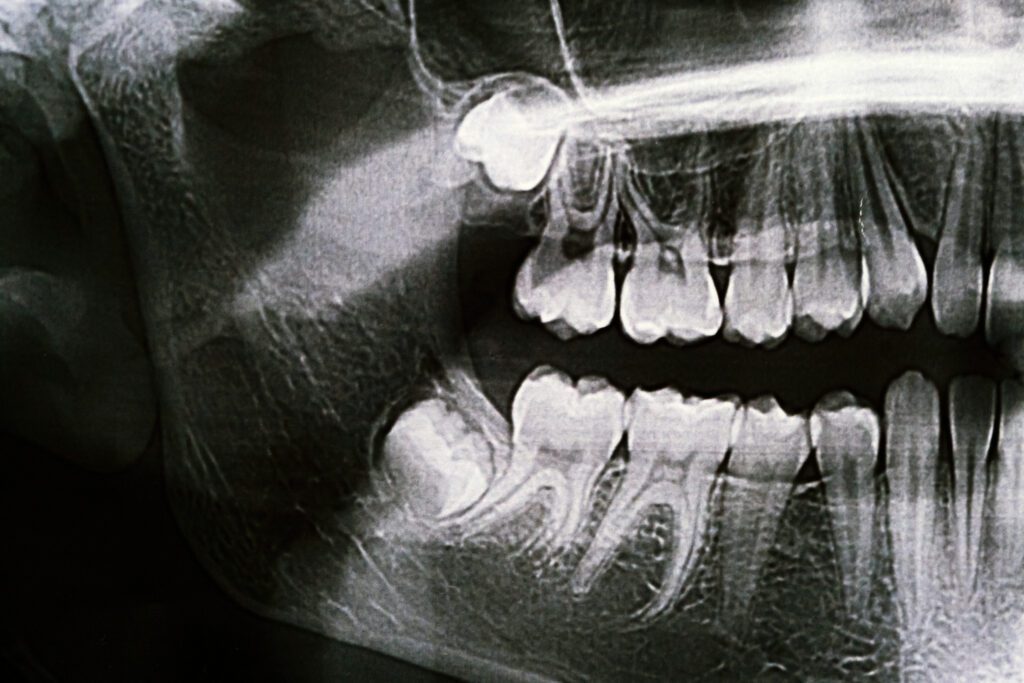

The average adult mouth is designed to hold around 28 teeth comfortably, but most adults end up with 32. The additional four teeth are called wisdom teeth, AKA third molars. The reason that some adults grow wisdom teeth is that throughout evolutionary history, the human jaw has become smaller and smaller. Because of this, the wisdom teeth become blocked or impacted by the other teeth around them. This can become extremely traumatizing. If the wisdom tooth partially erupts, food can get trapped in the tissue surrounding it, which can lead to bacterial growth and possibly serious infection.